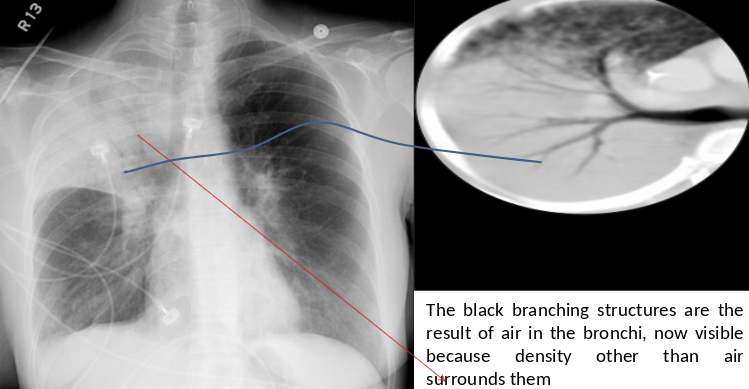

RT. lower lobe; Lobar pneumonia: Opacity of one or more pulmonary lobes & Presence of air bronchograms

- Right lower lobe is most commonly affected by pneumonia

- Spine blackness increased reversibly (Spine sign); lower part opaque

Bronchopneumonia:

- Poorly defined patchy infiltrates scattered throughout the lungs.

- Presence of air bronchograms

Air Bronchogram

Normally, it is not possible to identify air in bronchi within normally aerated lung, because the walls of the normal bronchi are too thin and air-filled bronchi are surrounded by air in the alveoli. However, if the alveoli are filled with fluid, the air in the bronchi contrasts with the fluid in the adjacent lung.